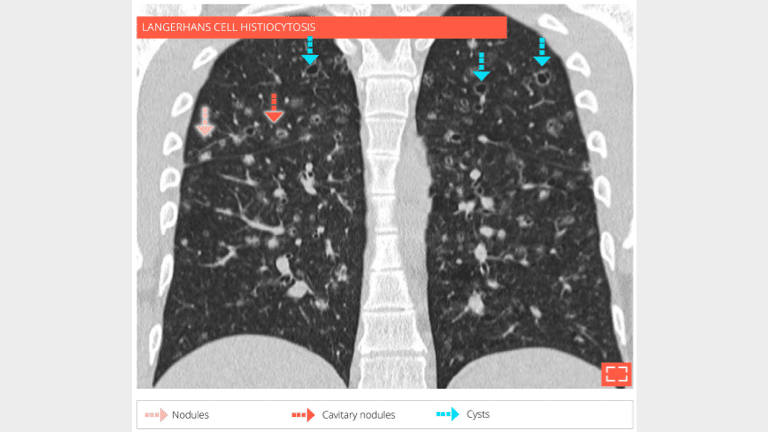

The patient is a 28-year-old male, smoker, with langerhans cell histiocytosis. HRCT at the level of middle zone shows bilateral and symetrical abnormalities of the lung parenclyma consisting in nodules, cavitated nodules, and cysts.

Same patient - coronal reformation shows that the abnormalities are predominating in the upper lungs.